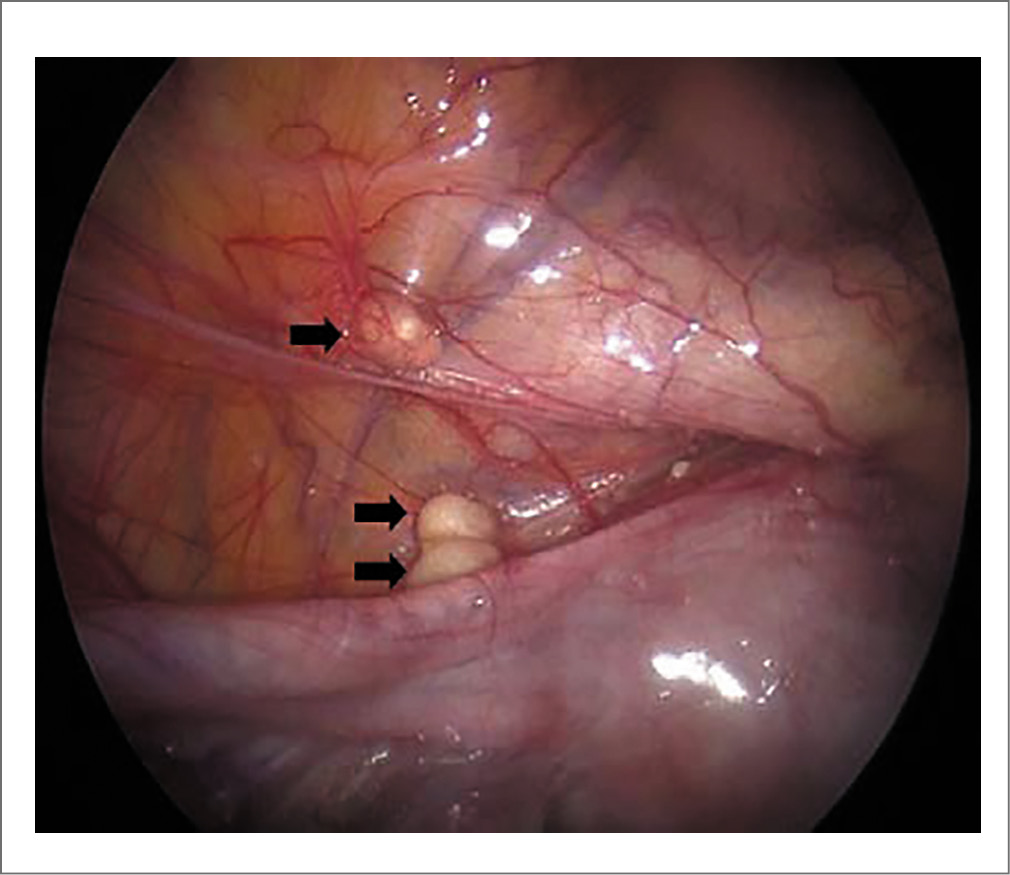

Типичная лапароскопическая картина при ТЖПО представлена на рис. 3, 4.

Рис. 3. ТЖПО, бугорки на теле матки (показаны стрелками). Источник: J. Sharma и соавт. [29]. / Fig. 3. FGT, tubercles on the uterine body (indicated by arrows) [29].